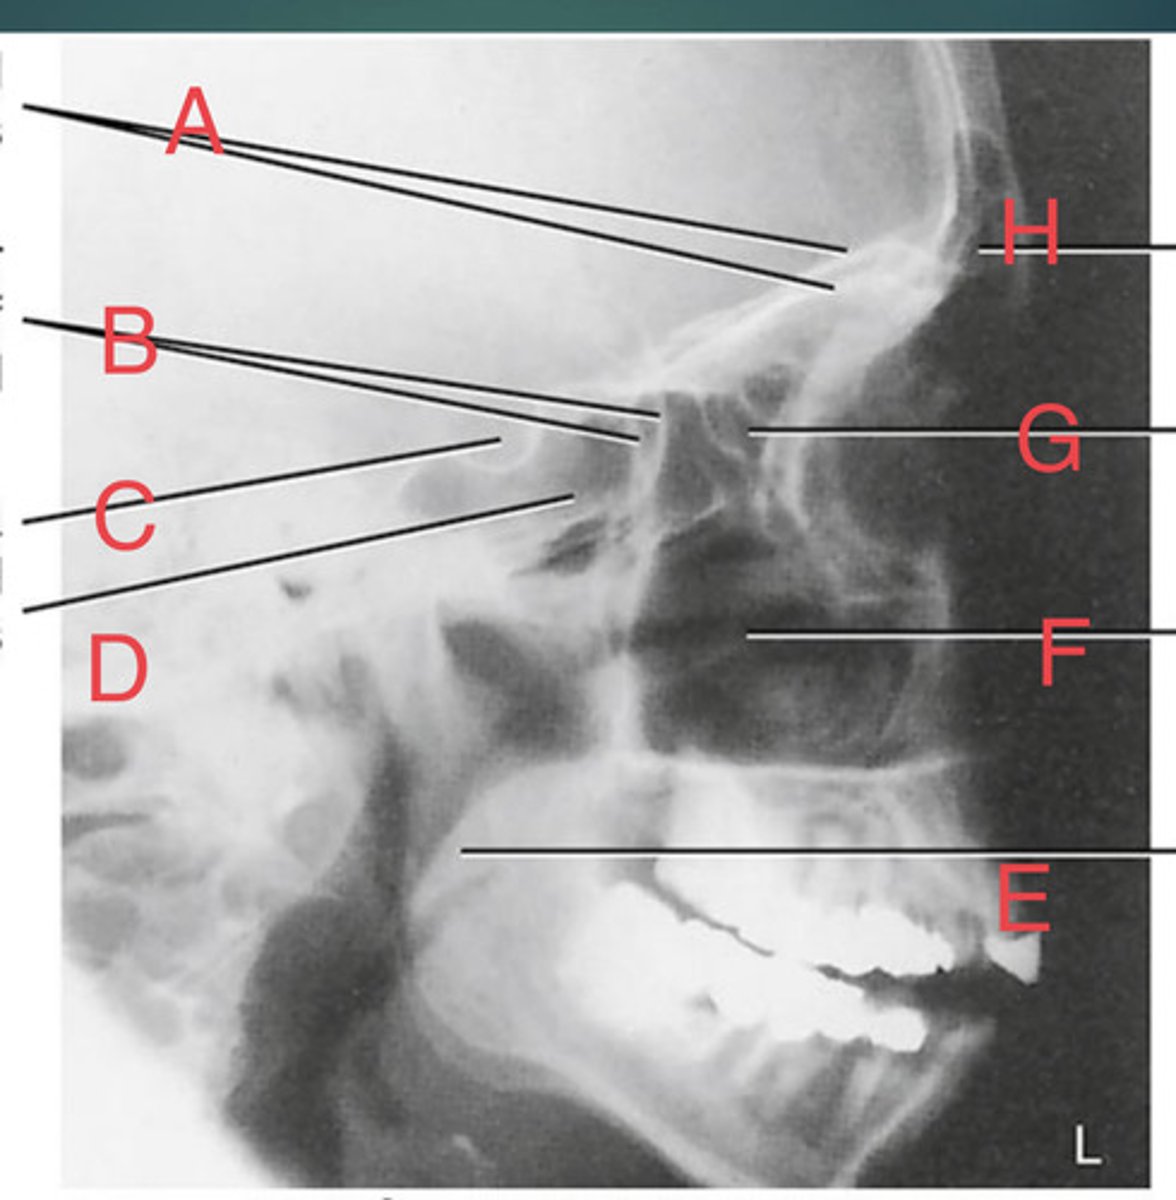

Lateral sinus

What position?

L. Orbital roofs

A.

L. Greater wings of sphenoid

B.

sella turcica of sphenoid

C.

L. Sphenoid sinus

D.

L. Rami of mandible

E.

L. Maxillary sinuses

F.

L. Ethmoid sinuses

G.

L. Frontal sinuses of frontal bone

H.